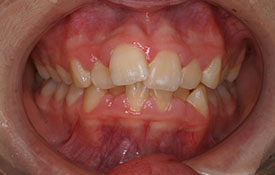

インビザラインの治療例:CASE-2

| プロフィール | 15歳 男性 |

| 所見 | アメリカから転院されて来られた方です。 インビザラインで上下顎の矯正治療を開始し下顎はアメリカで終了しており、上顎のみ治療の後期を担当しました。 アイライナーの装着は、1日平均22時間ほどでした。 |